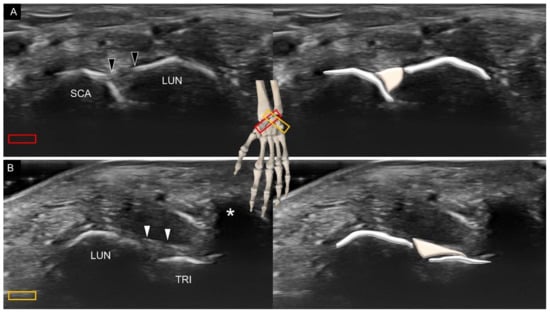

3. Sonoanatomy of Volar Extrinsic Carpal Ligaments

3.1. Attachment to the Capitate

3.2. Attachment to the Lunate

3.3. Attachment to the Triquetrum

4. Sonoanatomy of Volar Intrinsic Carpal Ligaments